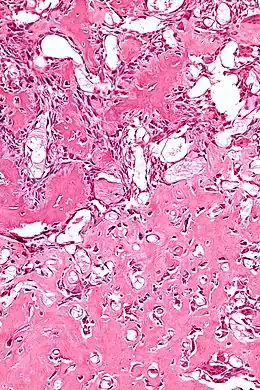

Vue histologique d'un ostéoblastome.

Histologiquement, les ostéoblastomes sont similaires aux ostéomes ostéoïdes, produisant de l'os au milieu du tissu conjonctif fibro-vasculaire. L'ostéoblastome peut atteindre plus de 2,0 cm de diamètre alors que les ostéomes ostéoïdes ne dépassent pas 2 cm.